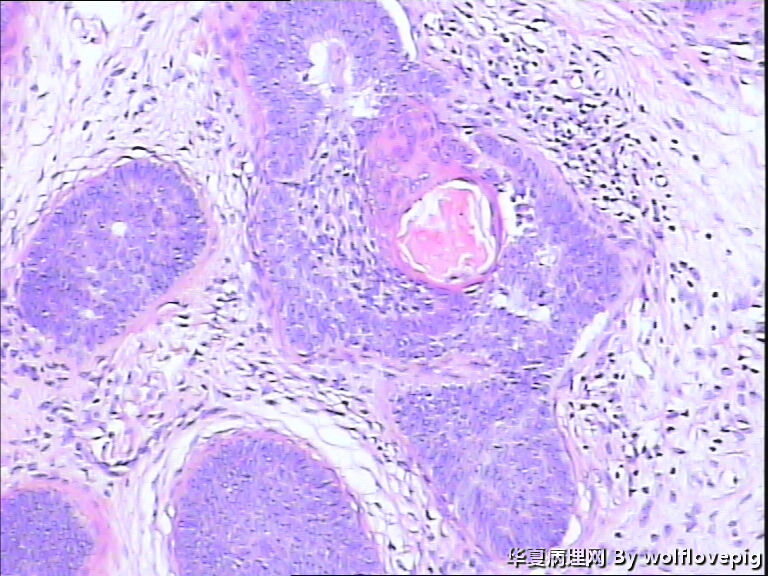

女,58y,右面部包块10年。灰白不整形带皮组织一块:2.3cm*1.5cm*0.3cm,切面有一灰白区域,质软,边界欠清。

诊断考虑毛母细胞瘤,或毛发上皮瘤。细胞团块周围可见嗜酸性纤维包绕,间质内纤维增生明显。

与表皮无关,表皮无破溃,无收缩间隙-------不支持BCC  有角囊肿 促纤维增生-----支持毛发上皮瘤